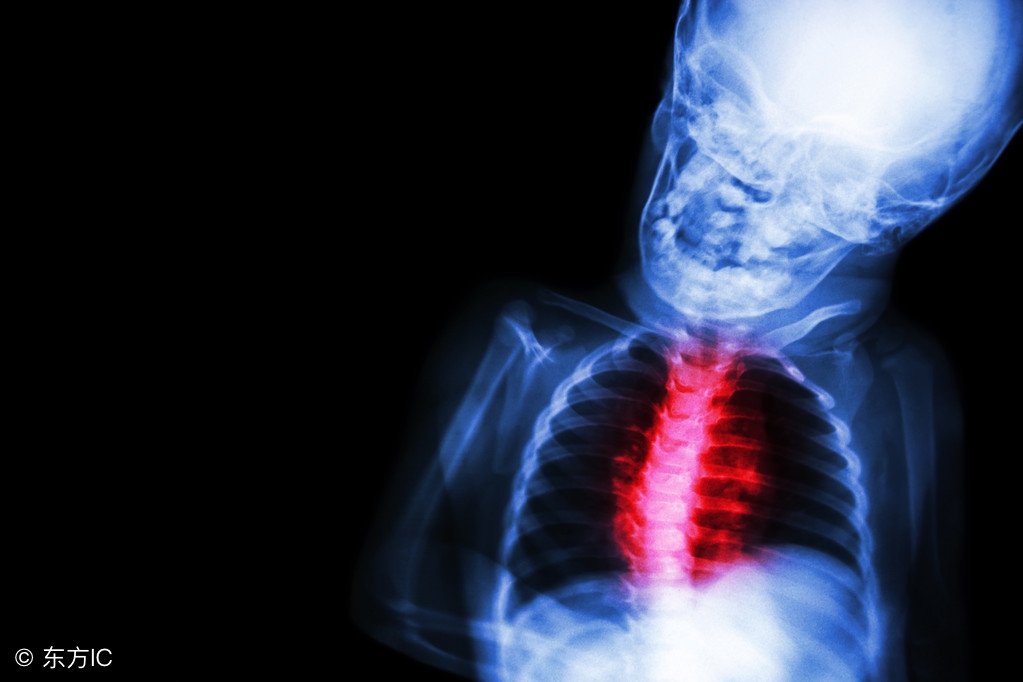

风湿性心脏病的症状有什么呢?风湿性心脏病简称风心病,是指因为风湿热流动,累及心脏瓣膜而造成的心脏病变。表现为二尖瓣、三尖瓣、主动脉瓣中有一个或几个瓣膜狭窄和(或)封闭不全。受损的瓣膜以二尖瓣为最常见,也可以几个瓣膜同时受累,称为联合瓣膜病变患病初期经常无显著症状,后期风湿性心脏病的症状则表现为心慌气短、乏力、咳嗽、肢体水肿、咳粉红色泡沫痰,直至心力衰竭而死亡。有的则表现为动脉栓塞以及脑梗塞而死亡。下面就介绍风湿性心脏病的症状有什么?生活中常见的风湿性心脏病症状表现有:

一、胸痛胸痛是风湿性心脏病症状中另一种常见的症状,可由多种原因引起,有时起源于局部轻微损害故无关重要,有时由于内脏疾病所致,根据胸痛的起源,可分为胸壁病变、胸腔器官疾病等及其他原因引起的胸痛,由心脏疾病引起的胸痛称为心原性胸痛。风湿性心脏病心瓣膜病引起的心绞痛,胸腔或心包受损等致的胸痛均属此列。